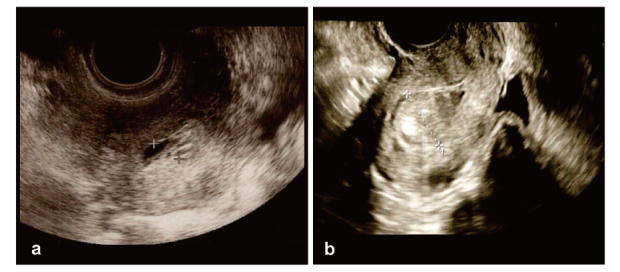

Von Willebrand disease (VWD) is a bleeding disorder caused by a congenital quantitative reduction, deficiency, or qualitative abnormality of the von Willebrand factor (VWF). Here, we report a case of delayed postoperative bleeding in an infertile woman with endometrial polyps complicated by VWD. The patient was a 39-year-old infertile woman with type 2A VWD. At 38 years of age, she was referred to our hospital for infertility and heavy menstrual bleeding. Hysteroscopy revealed a 15-mm polyp lesion in the uterus. The patient was scheduled for transcervical resection (TCR) of the endometrial polyp. Gonadotropin-releasing hormone agonists were preoperatively administered to prevent menstruation. The VWF-containing concentrate was administered for 3 days according to guidelines. The patient was discharged on postoperative day 3 after confirming the absence of uterine bleeding. Uterine bleeding began on postoperative day 6. The patient was readmitted on postoperative day 7 and treated with VWF-containing concentrate for 5 days, after which hemostasis was confirmed. TCR surgery for endometrial lesions is classified as a minor surgery, and guidelines recommend short-term VWF-containing concentrate replacement. However, it should be kept in mind that only short-term VWF-containing concentrate replacement may cause rebleeding postoperatively.